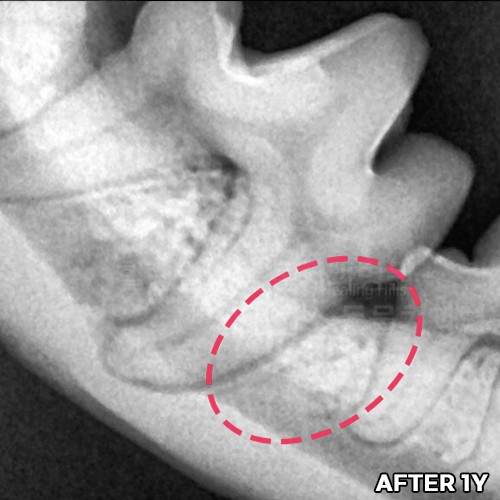

[강아지 잇몸에 고름] 최소침습적 발치 후 씨티로 확인된 자기잇몸뼈 증식! 치조골 살리는 힐링힐스 동물치과병원

2025.10.27